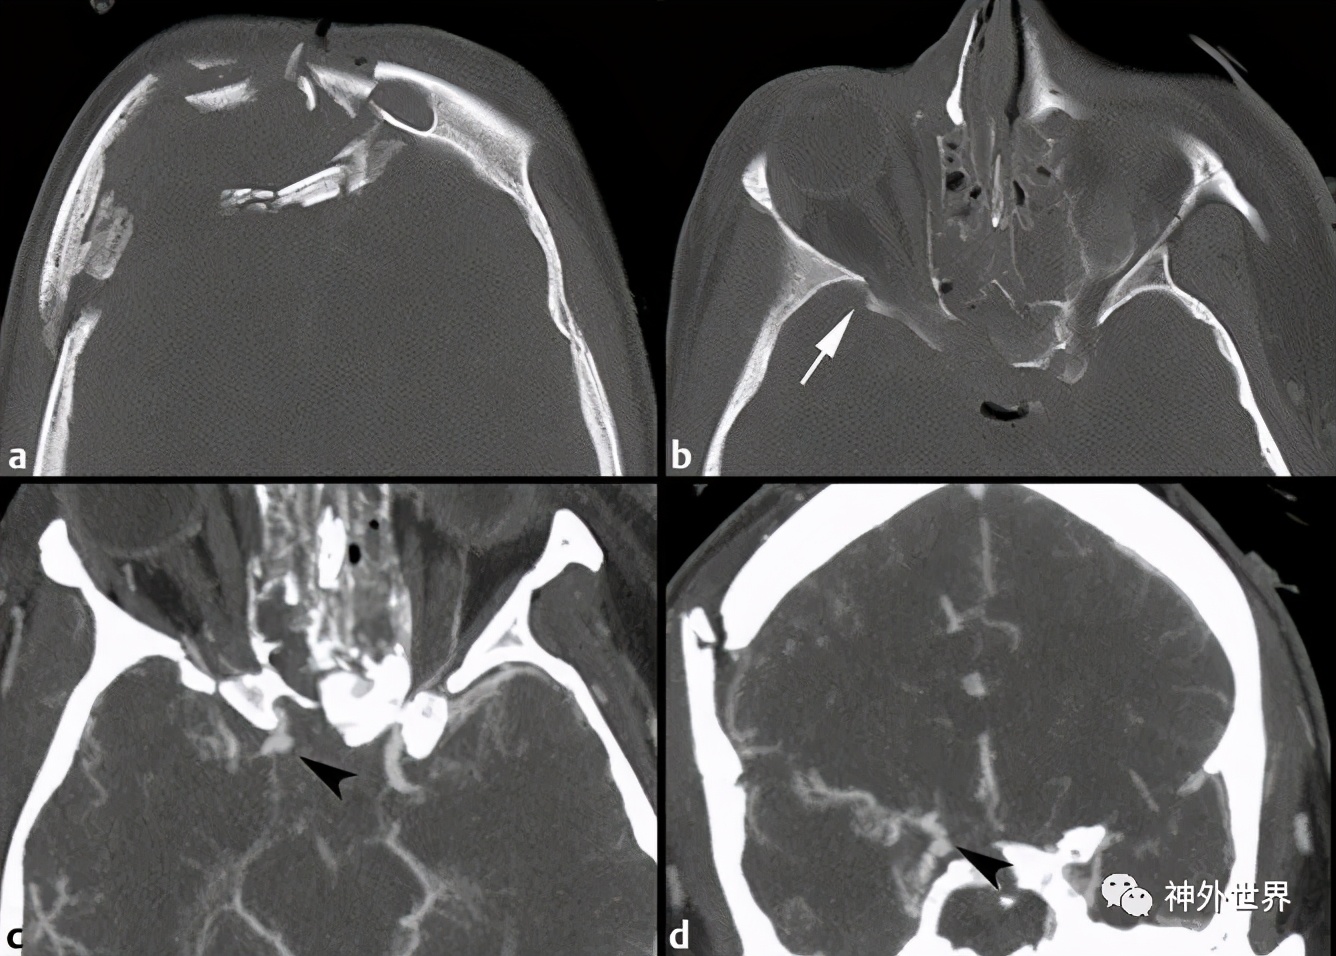

图10:前颅底骨折合并血管损伤。A, CT示右侧额骨严重粉碎性骨折;B,骨折延伸到蝶骨大翼(箭头),累及筛窦和蝶窦壁;C,CT血管造影(C)和冠状动脉重建(D)示创伤性右颈内动脉假性动脉瘤(黑箭头)